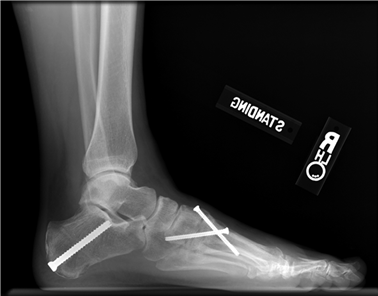

Clinical & Radiographic Imaging Archive

Clinical Image